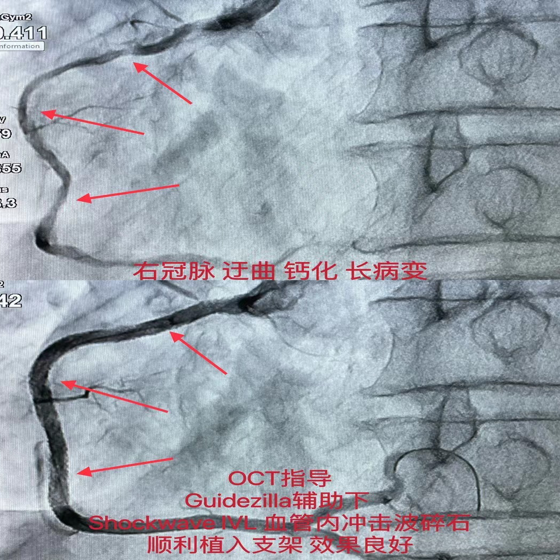

该患者于10天前,于我院开通前降支无残端CTO,右冠脉迂曲、弥漫长病变伴严重钙化,此次在OCT指导下,Guidezilla延长导管辅助下,送入Shockwave IVL冲击波球囊于病变处予8个周期80个脉冲的预处理后顺利植入支架,复查OCT结果满意,未见支架膨胀不全及贴壁不良。

根据标准操作流程,充盈4atm使球囊充分贴靠,从第一次球囊冲击波发射2个周期后,更换位置,连续8个周期以后,钙化部位球囊凹陷处消失并可正常膨胀,狭窄减轻。

术中连续治疗8个周期(80次脉冲)后,植入支架,支架贴壁良好。

冠状动脉血管内冲击波碎石技术Shockwave IVL是基于治疗泌尿系结石的碎石理念结合球囊成形术进行创新性研发的新技术,可通过球囊内脉冲产生声压力波选择性作用内膜及中膜下的钙化病灶,使钙化松解却不影响血管内膜的完整性,达到钙化斑块修饰的效果,扩大管腔面积,为后续的支架置入和展开提供充分的条件,也弥补了目前对于严重钙化病变预处理技术的一些不足。